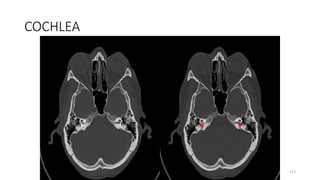

COCHLEA

212

INTERNAL AUDITORY CANAL

Content

BASAL TURN OF COCHLEA